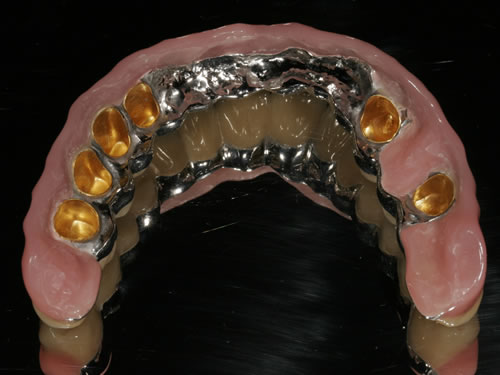

Wenn viele Zähne fehlen und nur noch einige erhaltungswürdige Zähne vorhanden sind, die in den neuen Zahnersatz mit einbezogen werden können, dann spricht man von einer reduzierten Bezahnung. Die prothetische Versorgung wird als Hybridkonstruktion bezeichnet, da sie sowohl auf natürlichen Zähnen als auch auf Implantaten befestigt wird. Die Versorgung kann sowohl festsitzend - verschraubt oder zementiert - gestaltet werden (Abb. 3.24, 3.25), aber auch herausnehmbar, wobei dann häufig teleskopierende Konzepte verwendet werden (Abb. 3.26, 3.27).

Abb. 3.26: Hybridversorgung einer reduzierten Oberkieferbezahnung auf 4 Zähnen und 3 Implantaten.

Abb. 3.27: Ansicht des gaumenfreien, herausnehmbaren Zahnersatzes.